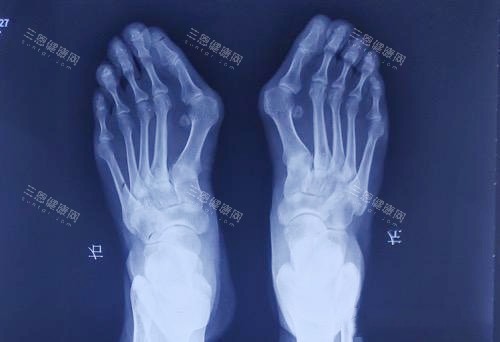

身边好多人受拇指外翻困扰 —— 穿鞋磨脚、走路疼,有的甚至影响运动和日常。

基本情况:遗传妈妈的拇指外翻,右边比左边重,穿平底鞋都磨脚,怕影响以后穿婚鞋

基本情况:拇指外翻 15 年,现在晚上睡觉都能疼醒,关节也有点变形,儿女催我做手术

基本情况:拇指外翻 20 年,试过矫正器、**泡脚都没用,现在疼得走不了远路,只能做手术